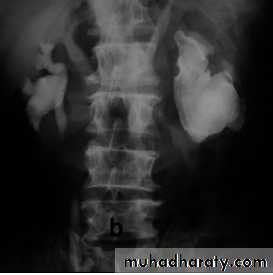

KUB

The post contrast series:

IV access is required for administration of the contrast material.The contrast dose is usually instilled at a fast (bolus) rate.

The calyces are usually not visualised in <2 minutes following contrast administration - This is the NEPHROGRAM phase.

Serial images are taken at 5-20 minutes for visualisation of the PCS and ureters…This is the PYELOGRAM or EXCRETORY phase.

Lastly take a full bladder and a post-void film.